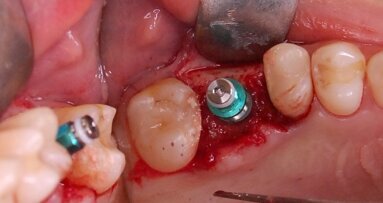

Zabieg od strony podniebienia rozpoczynano nacięciem na grzbiecie wyrostka, który przedłużano w okolicy zębów przedtrzonowych skośnie do przodu i mezjalnie (Ryc. 1a i b). Płat ustabilizowano przy pomocy szwu lejcowego, co zapewniało dobry wgląd w pole operacyjne. Etap wykonania okienka kostnego przeprowadzono przy pomocy urządzenia piezoelektrycznego (Ryc. 2a i b). Następnie odpreparowano fragment blaszki kostnej, którą po wprowadzeniu materiału kościozastępczego położono w miejscu, skąd został wycięty. Płat zreponowano bez podcinania okostnej, nie stosując membran zaporowych, po czym ranę zszyto nićmi resorbowalnymi (Ryc. 3). Analogicznie zabieg wykonano od strony przedsionka w klasyczny sposób.

Ryc. 1a_Nacięcie i odwarstwienie płata śluzówkowo-okostnowego. Cięcie rozpoczęto na szczycie wyrostka, w okolicy kła/zębów przedtrzonowych wykonano cięcie uwalniające.

Ryc. 1b_Nacięcie i odwarstwienie płata śluzówkowo-okostnowego. Cięcie rozpoczęto na szczycie wyrostka, w okolicy kła/zębów przedtrzonowych wykonano cięcie uwalniające.

Ryc. 2 a_Wytworzenie okna kostnego od strony podniebiennej, uwidaczniając nienaruszoną membranę Schneidera.

Ryc. 2 b_Wytworzenie okna kostnego od strony podniebiennej, uwidaczniając nienaruszoną membranę Schneidera.